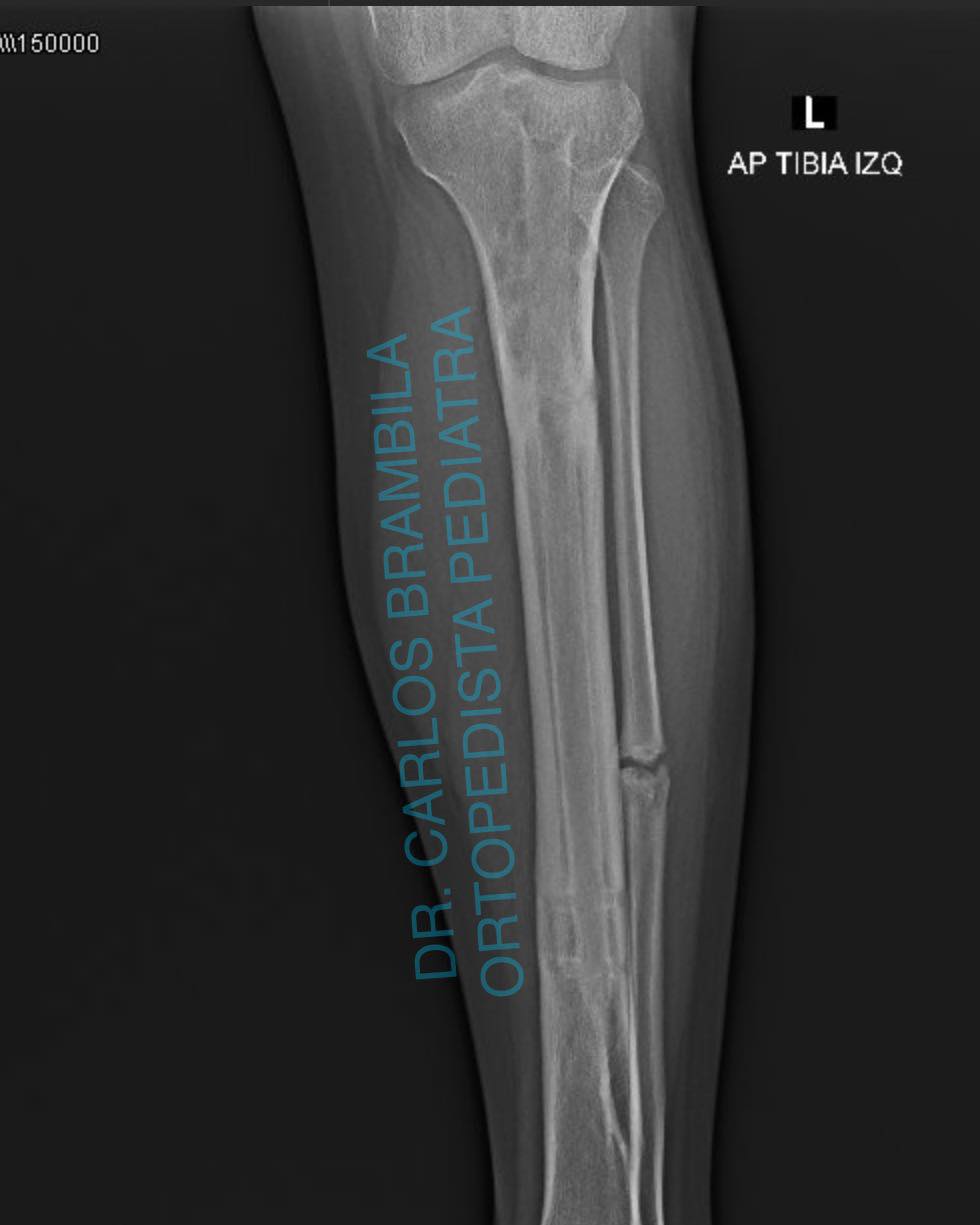

Me complace compartir con ustedes el caso de Karen, una joven de 17 años que acudió a mi consulta por un acortamiento en su extremidad inferior izquierda debido a una fractura de tibia. Después de una evaluación clínica y radiográfica, le realicé una cirugía de alargamiento óseo guiado con clavo centro medular y fijador externo Rekrea. El procedimiento fue un éxito, y Karen recuperó el balance de sus extremidades, eliminando el dolor en su cadera derecha. Ahora, Karen puede realizar todas sus actividades físicas sin problemas y se va feliz y satisfecha. Me siento orgulloso de haber podido ayudarla a recuperar su calidad de vida.